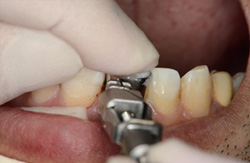

もってきた折れた歯冠の戻り具合(位置、方向)をまず確認します。 |

![]() |